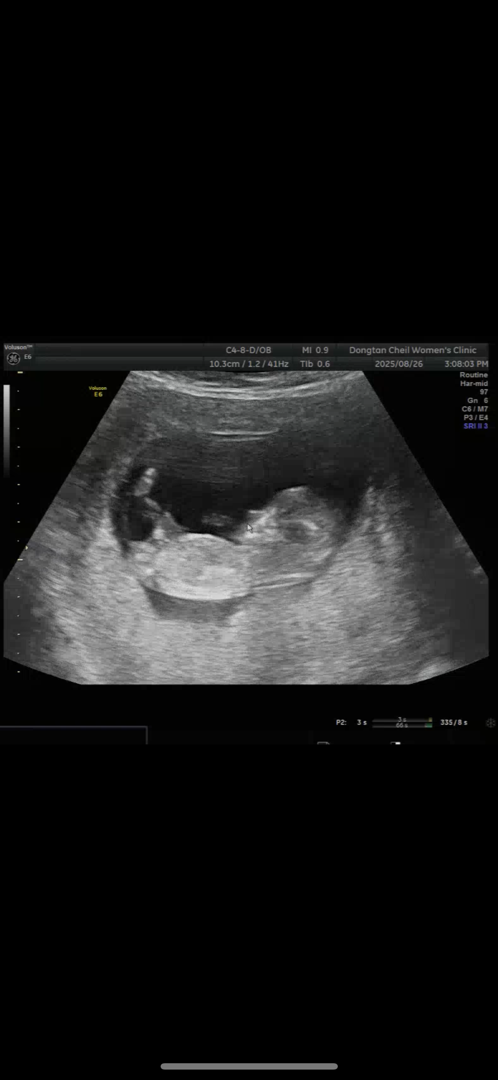

12주차 각도법

오늘 11주차4일차에 1차 기형아검사 하고 왔습니다 ㅎㅎ 목투명대1.6이라고 하네요 ㅠㅠㅠ 혹시 이사진으로 성별 알수있을까요? ㅠㅠ 너무궁금하네요🍼🥹